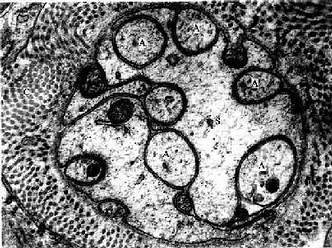

图7-19 大鼠无髓神经纤维横切电镜像×45000

A轴突,S施万细胞,C胶原原纤维

(白求恩医科大学尹昕、朱秀雄教授供图)